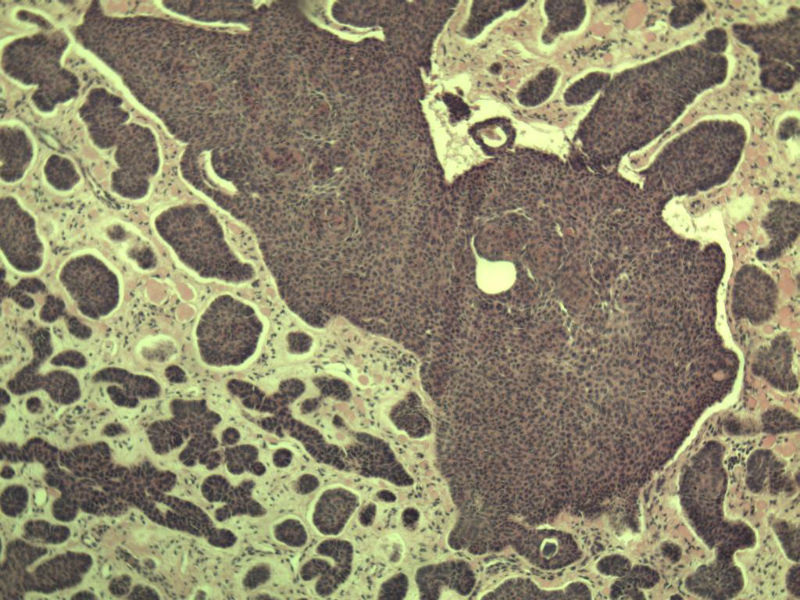

女 67岁 临床考虑面部色素痣 1*0.8 cm  请问各位老师 这是什么? 谢谢!面部包块图1

毛母/发细胞瘤鉴别基底细胞癌,可做CD10,CK7,CK20鉴别

考虑毛发上皮瘤,需除外基底细胞癌。

毛发上皮瘤,需与基底细胞癌鉴别

第一例:毛发上皮瘤

第一例:毛发上皮瘤,与基底细胞瘤区别明显。

第一例  毛发上皮瘤,和基底细胞癌鉴别一下

第一例考虑毛母细胞瘤,第二例考虑基底细胞癌。

第一例:毛母细胞瘤;第二例:基底细胞癌

第一例,毛发上皮瘤;第二例,基底细胞癌。

一毛发上皮瘤